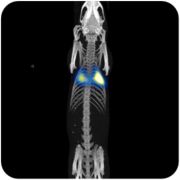

MPI磁粒子小动物活体成像性能优势 1. 易转化到人,用临床SPIO示踪剂。 2. Nm级灵敏度,可检测个位数细胞。 3. Mm级分辨率,目前达到0.3mm。 4. 信号不随深度衰减,3D断层扫描。 5. 可以长达数个月的连续示踪成像。 6. SPIO无毒无放射,代谢成血红素。 7.定量分析。 主要应用 多模态成像;活体成像;干细胞及各种类细胞示踪;肿瘤检测示踪(肿瘤微环境/肿瘤免疫微环境);免疫炎症示踪;心脑血管成像;血管灌注成像;准确靶向磁热疗;准确靶向药物输送;肿瘤免疫治疗(局部免疫刺激);纳米粒子开发。 肿瘤免疫治疗是全球趋势 临床应用前景 1.得到美国NIH的资金支持,正在合作研发可用于临床的MPI. 2. 区别于CT、MRI、和PET等,MPI成像没有任何辐射,不需要使用任何有毒性的示踪剂。使用临床许可的超顺磁性氧化铁纳米颗粒(SPIO):安全性通过临床审查,特别是可用于肾功能不全或肾脏损伤的病人。 3. SPIO这种纳米尺寸的氧化铁粒子在体内可以分解并转化为血红素,完全的支持长期诊断检测,无任何累计辐射或毒性。 |